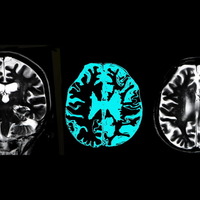

レカネマブのお世話になる前に──アルツハイマー病を防ぐため脳の老廃物を洗い流す科学的な方法とは

厚労省は9月下旬、アルツハイマー病の進行を緩やかにする効果を証明したとされる新薬の製造販売を承認した。そもそもこの病にかかりにくくするにはどうしたらいいのか。脳神経科学者でお茶の水大学助教の毛内拡さん...